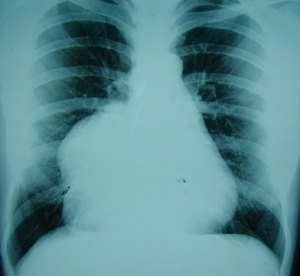

Περίπτωση Νο 2

Εικόνα 2

Πλάγια ακτινογραφία του θώρακος. Υπάρχει ευμεγέθης όγκος στην οπισθοστερνική περιοχή, στο επίπεδο της ξιφοειδούς απόφυσης.

Εικόνα 3

Η αξονική τομογραφία του θώρακος επιβεβαιώνει τα ευρήματα της απλής ακτινογραφίας του θώρακος και αναδεικνύει την ύπαρξη του όγκου του θωρακικού τοιχώματος προερχόμενο από την στερνοπλευρική γωνία στο ύψος της ξιφοειδούς απόφυσης. Ο όγκος έχει αποτιτανώσεις.